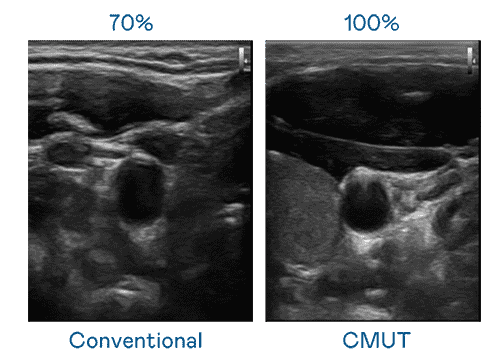

CMUT 技术是一种用电容式微机电元件来产生超音波讯号的技术。。。与传统 PZT 压电式技术相比,,,CMUT 频宽增加 30%,,,,更宽频的超音波讯号让影像解析度大幅提升,,,是实现高影像品质医疗超音波扫描、、、、促进精准医疗发展的关键技术。。

大频宽带来超清晰影像

超音波影像的解析度高低,,,首先取决于探头能发出的讯号频宽。。。。z6尊龙 CMUT 可提供高清晰的超音波讯号,,,,提供高频宽、、、、高灵敏度、、、影像纹理细节更高的超音波影像,,,,协助医护人员缩短影像判读时间及利用精准的医疗影像进行诊断。。。